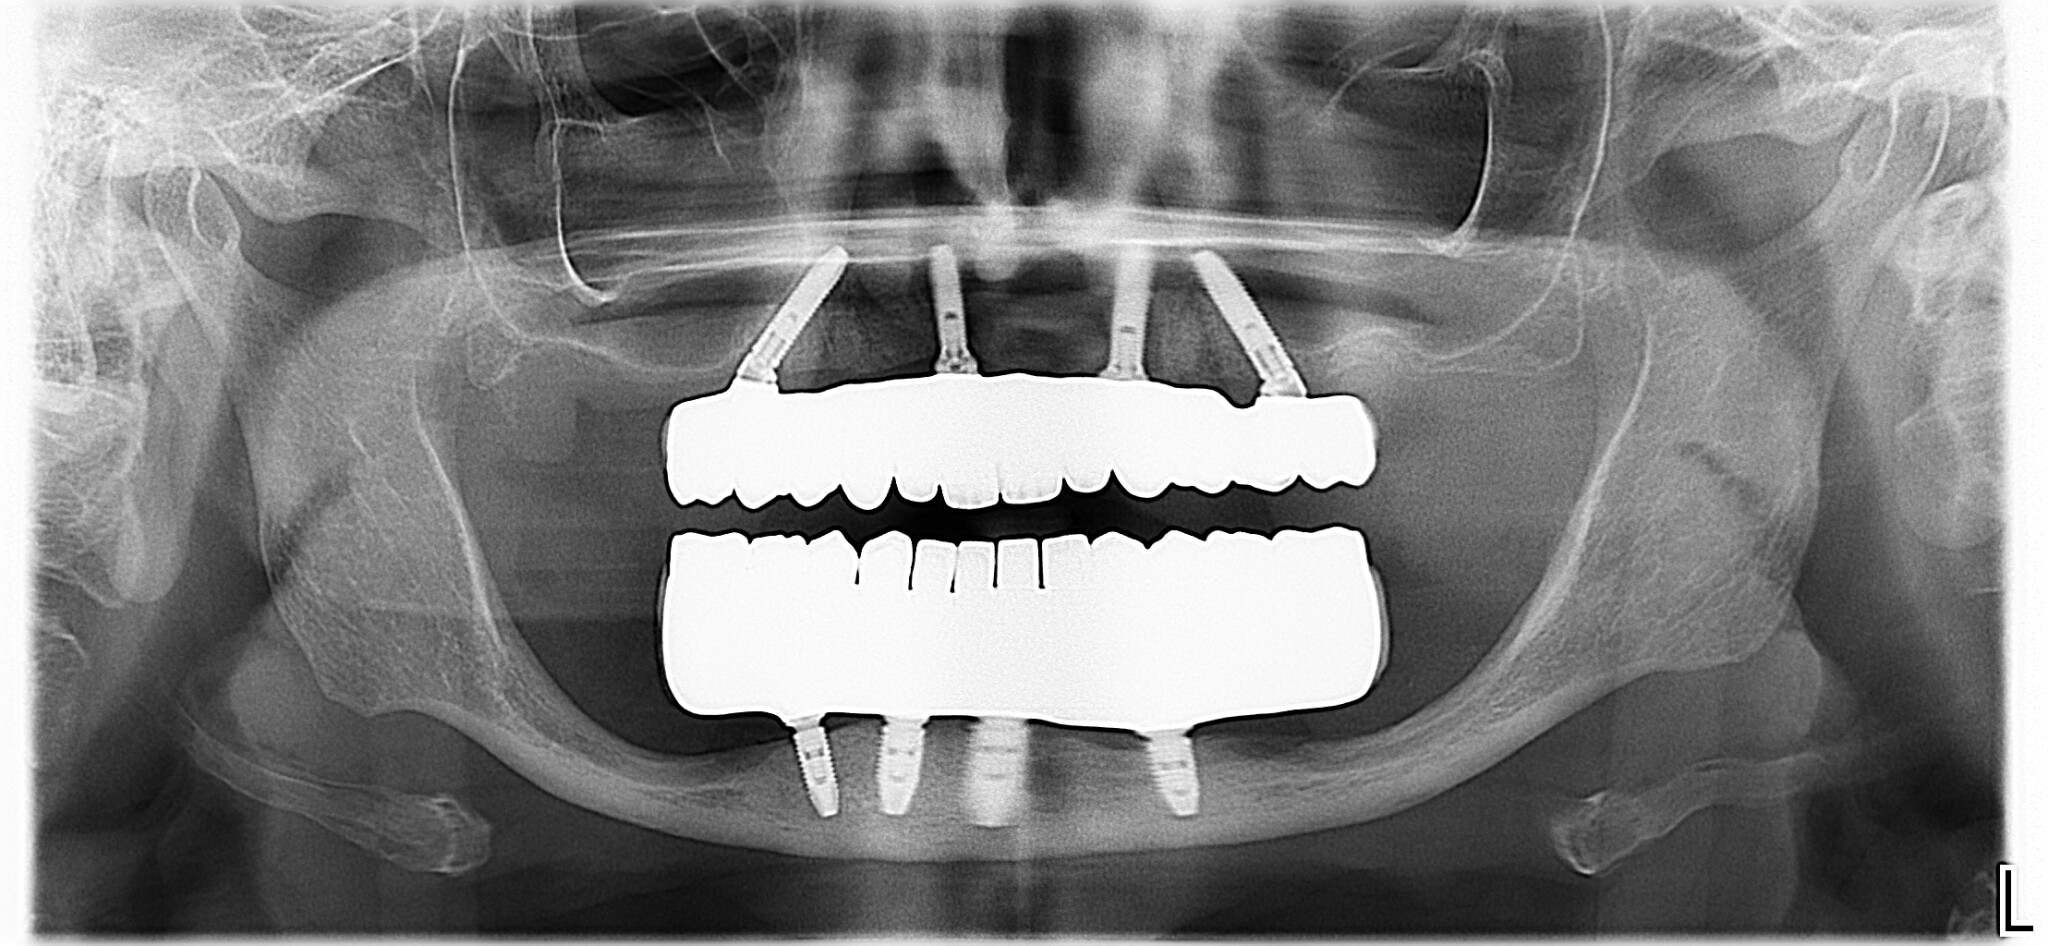

Panoramica

Oggi siamo a 3 anni di follow-up e la paziente è una delle nostre principali sostenitrici, non perde occasione di farci pubblicità e di portarci altri pazienti.